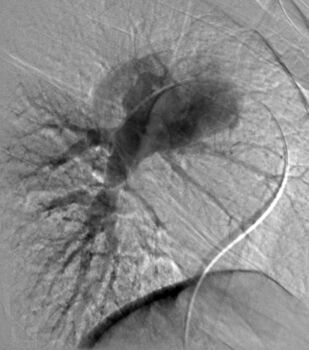

В четвертом томе четырехтомного руководства по кардиологии описываются этиология, патогенез, диагностика, клиническое течение и лечение сердечно-сосудистых заболеваний, в частности сердечной недостаточности, миокардитов, кардиомиопатий, легочной артериальной гипертензии, приобретенных пороков сердца, инфекционного эндокардита, перикардитов, опухолей и травм сердца, болезней сосудов. Приводятся также сведения об основных классах лекарственных препаратов, применяемых для лечения сердечно-сосудистых заболеваний. Руководство предназначено для кардиологов, терапевтов, врачей общей практики (семейных врачей), кардиохирургов, специалистов по рентгеноэндоваскулярной диагностике и лечению, врачей других специальностей, принимающих участие в обследовании и лечении больных с заболеваниями сердечно-сосудистой системы, и студентов высших медицинских учебных заведений.